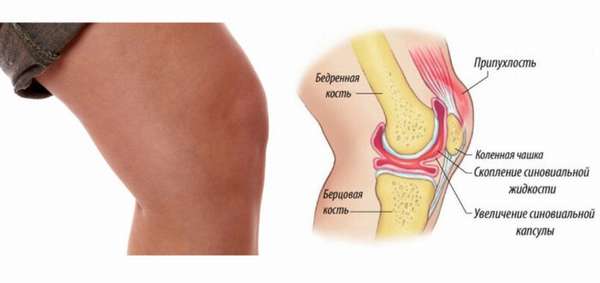

Заболевания и медицинские снимки: Жидкость в коленной чашечке

Раздел: Галерея прозрений